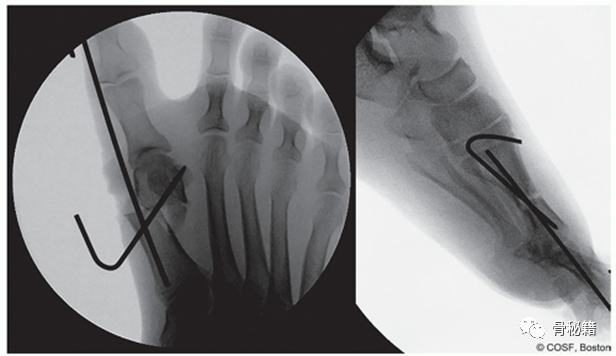

透视图像显示了计划的截骨位置。

计划的切口位置。钢丝不应穿透骨骼,应保持在骨膜外平面。

透视用于确认 HVA、IMA 和 DMAA 的矫正,并用驱动器或槌从远端到近端沿着第一跖骨的髓管驱动导丝。导线被驱动到跖骨的底部,并且可以在骨骼未成熟的患者中穿过骨骺推进

透视图像和照片,说明使用矢状锯进行跖骨截骨术。注意切口轨迹垂直于第二跖骨轴。

针在拇趾软组织骨外位置的透视图像。

应获得额外的侧位图像以确保跖骨头在矢状面上的适当位置。如果头部已经向足底或背侧平移,则可以调整导线在截骨水平的位置以确保它在中线

最终透视图像,说明用于旋转和足底/背侧平移控制的第二个斜针。横向显示截骨的对齐。